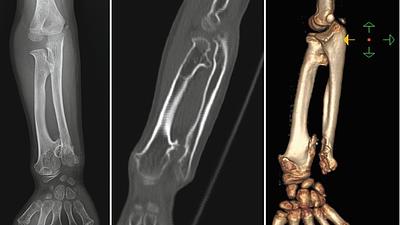

saudecirurgia.jpg

Entenda a condição neurológica que motivou cirurgia de Chico Buarque

04/06/2025, 11:51

A condição ocorre quando há excesso de líquor, fluido que reveste o sistema nervoso central, acumulado no cérebro, mas sem provocar aumento da pressão intracraniana.